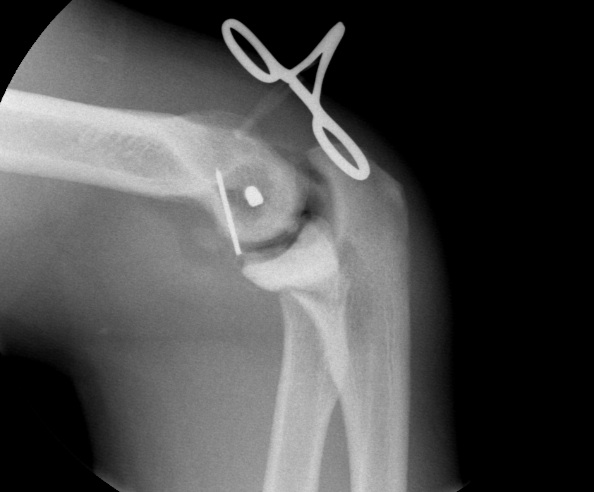

Distal humeral axis

- confirm center of rotation on lateral

- protect ulna nerve

- place guide wire in center of rotation